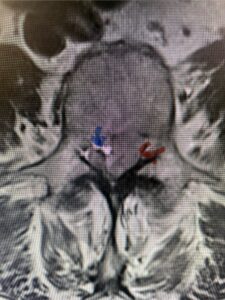

Fig 1b: Axial lumbar T2-weighted MRI demonstrating severe lumbar stenosis (red dot)

Fig. 3b: Axial T2-weighted lumbar MRI demonstrating severe compression of the thecal sac (blue arrow) by the large left sided disc herniation (red arrow) taking up most of the left side of the spinal canal (red arrow)